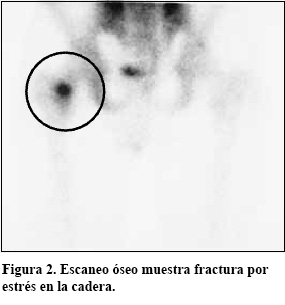

Para confirmar una fractura por tensión, puede que su médico le ordene una radiografía (ver Figura 1). Si la radiografía no muestra una fractura por tensión, puede necesitar realizar una gammagrafía ósea (ver Figura 2) o una resonancia magnética (IRM).